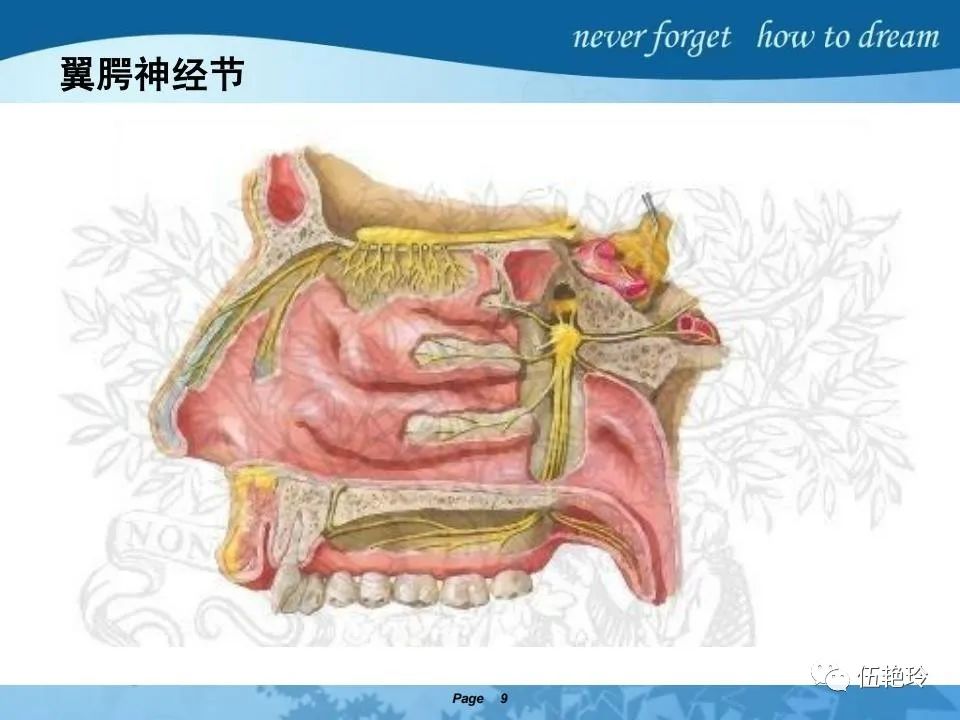

翼腭窝的解剖结构与鼻咽癌侵犯

2.2 鼻咽特有的解剖途径:鼻咽癌原发灶循序进展的总途径:鼻腔(47.8%)→翼腭窝(15.2%)→ 眶下裂(3.2%)→眶尖(1.2%)→海绵窦(0.6%)。

2.31 向上颅内:①鼻咽顶壁→破裂孔(岩尖、斜坡)→蝶窦、海绵窦;②鼻咽顶壁→蝶骨基底部→蝶窦、海绵窦;③鼻咽侧壁→茎突前间隙→蝶骨大翼(卵圆孔)→海绵窦;④鼻咽侧壁→茎突前间隙→翼腭窝→ 颞下窝;⑤鼻咽前壁→鼻腔→翼突、翼腭窝→眶下裂→眶尖→海绵窦;⑥鼻咽前壁→鼻腔→上颌窦、筛窦;